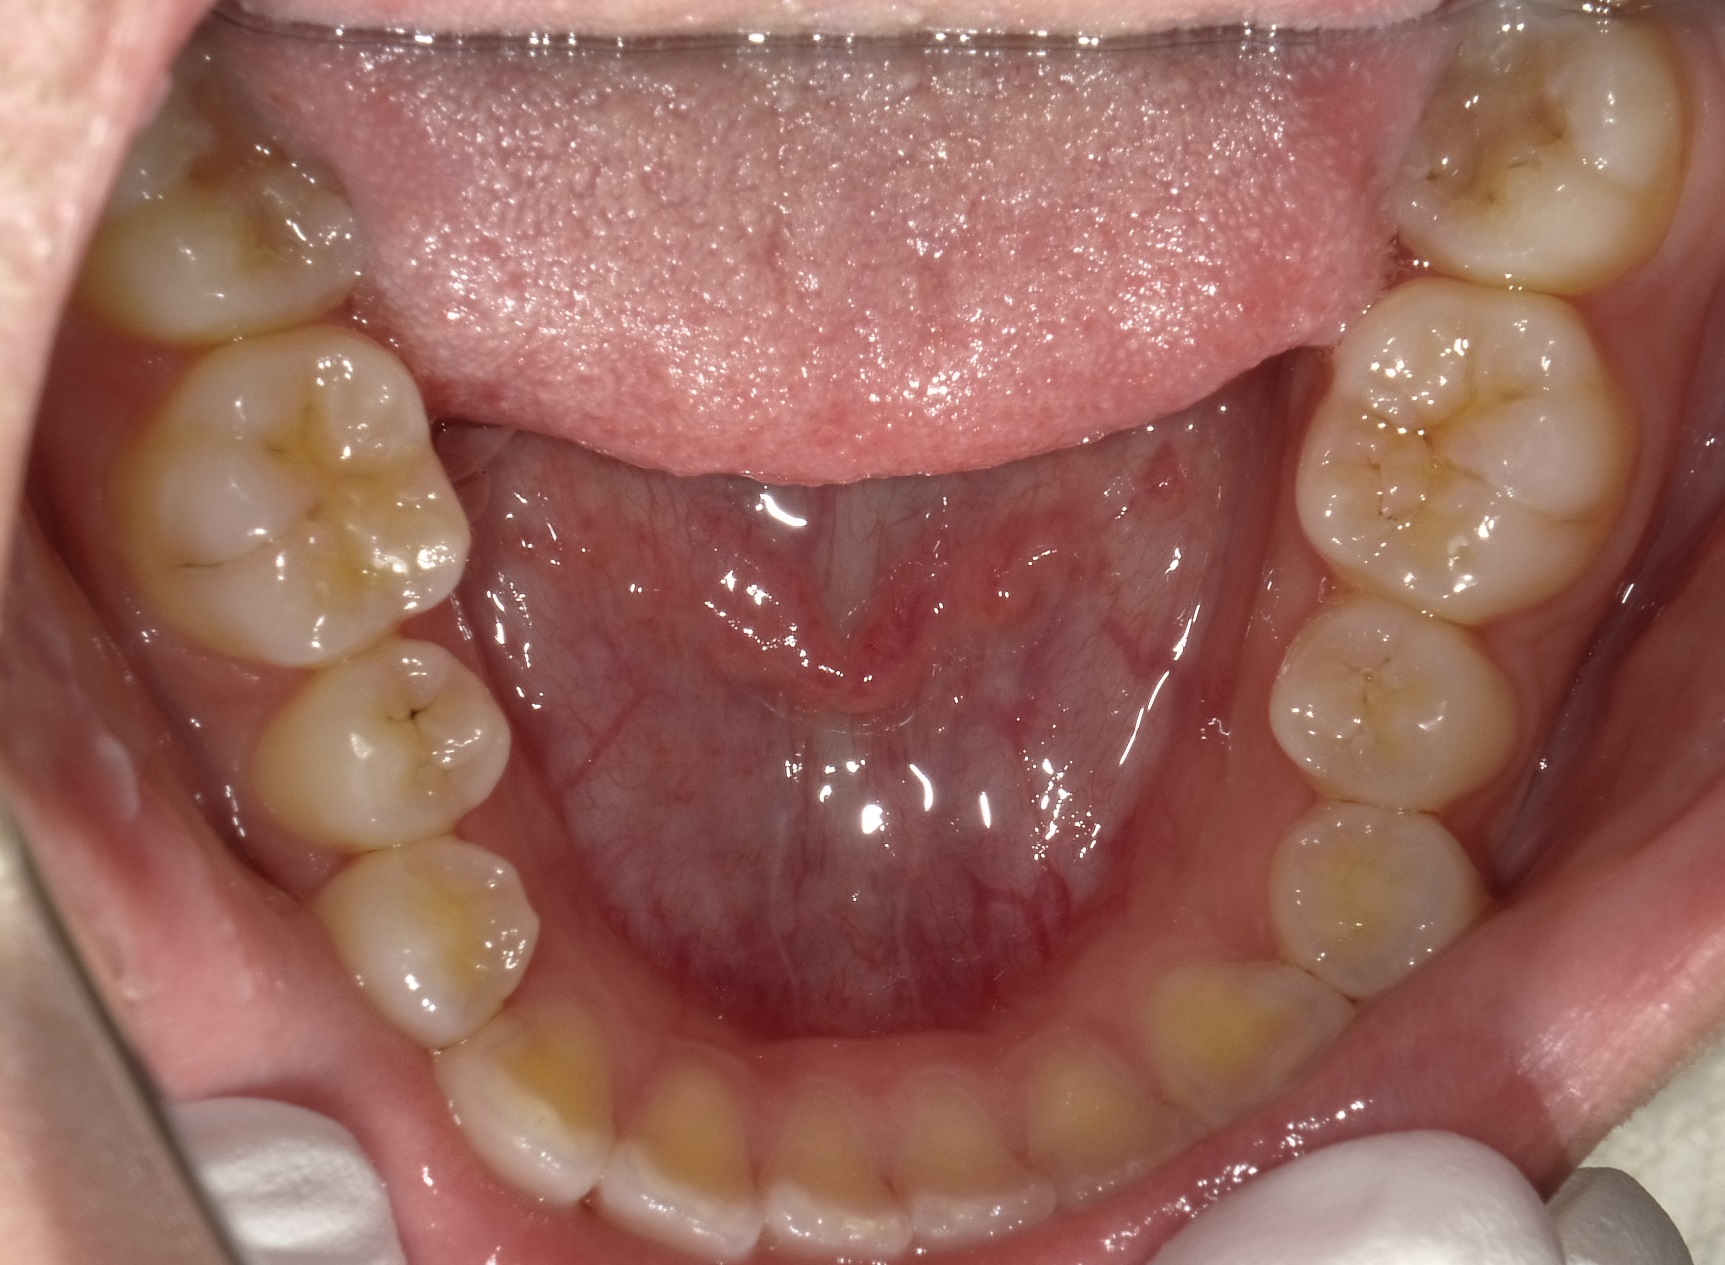

次は上下の歯列の写真です。

これだけ見ると、上は少しの並びの悪さ、下に関してはほとんど問題ないのですが、このままだと上記のとおり噛み合わせたときにお互いぶつかってしまうため、右上前歯の引っ掛かりを取り除き、歯並びおよび噛み合わせ、下顎の受け口感、左右差を治していきます。